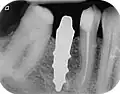

Область с единственным отсутствующим зубом

Через десну делается разрез, и лоскут ткани откидывается, чтобы показать кость челюсти.

Как только кость обнажена, серия упражнений создаёт и постепенно увеличивает участок (называемый остеотомией) для установки имплантата.

Крепление имплантата превращается в остеотомию. В идеале он полностью покрыт костью и не имеет движения внутри кости.

Формирователь десны (опора для заживления) прикрепляется к креплению имплантата, а лоскут десны накладывается на заживляющий абатмент.